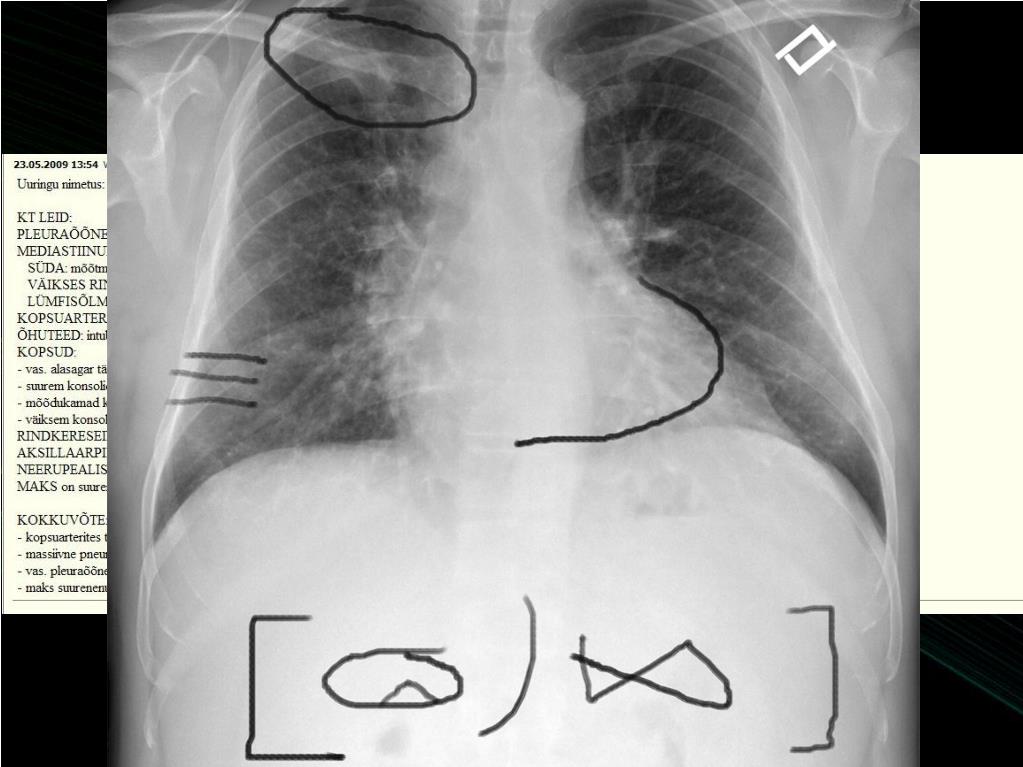

18. Vastuse edastamine raviarstile • Juhuleiuna • Kopsuarteri trombemboolia • Ümarvari kopsus • Kas te helistate? • ACR: peab teavitama